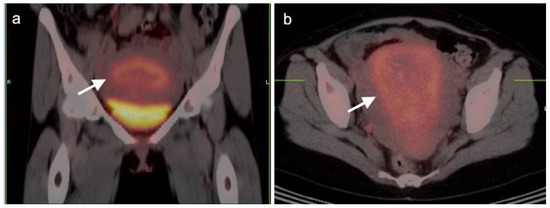

2.4. Cervical Cancer